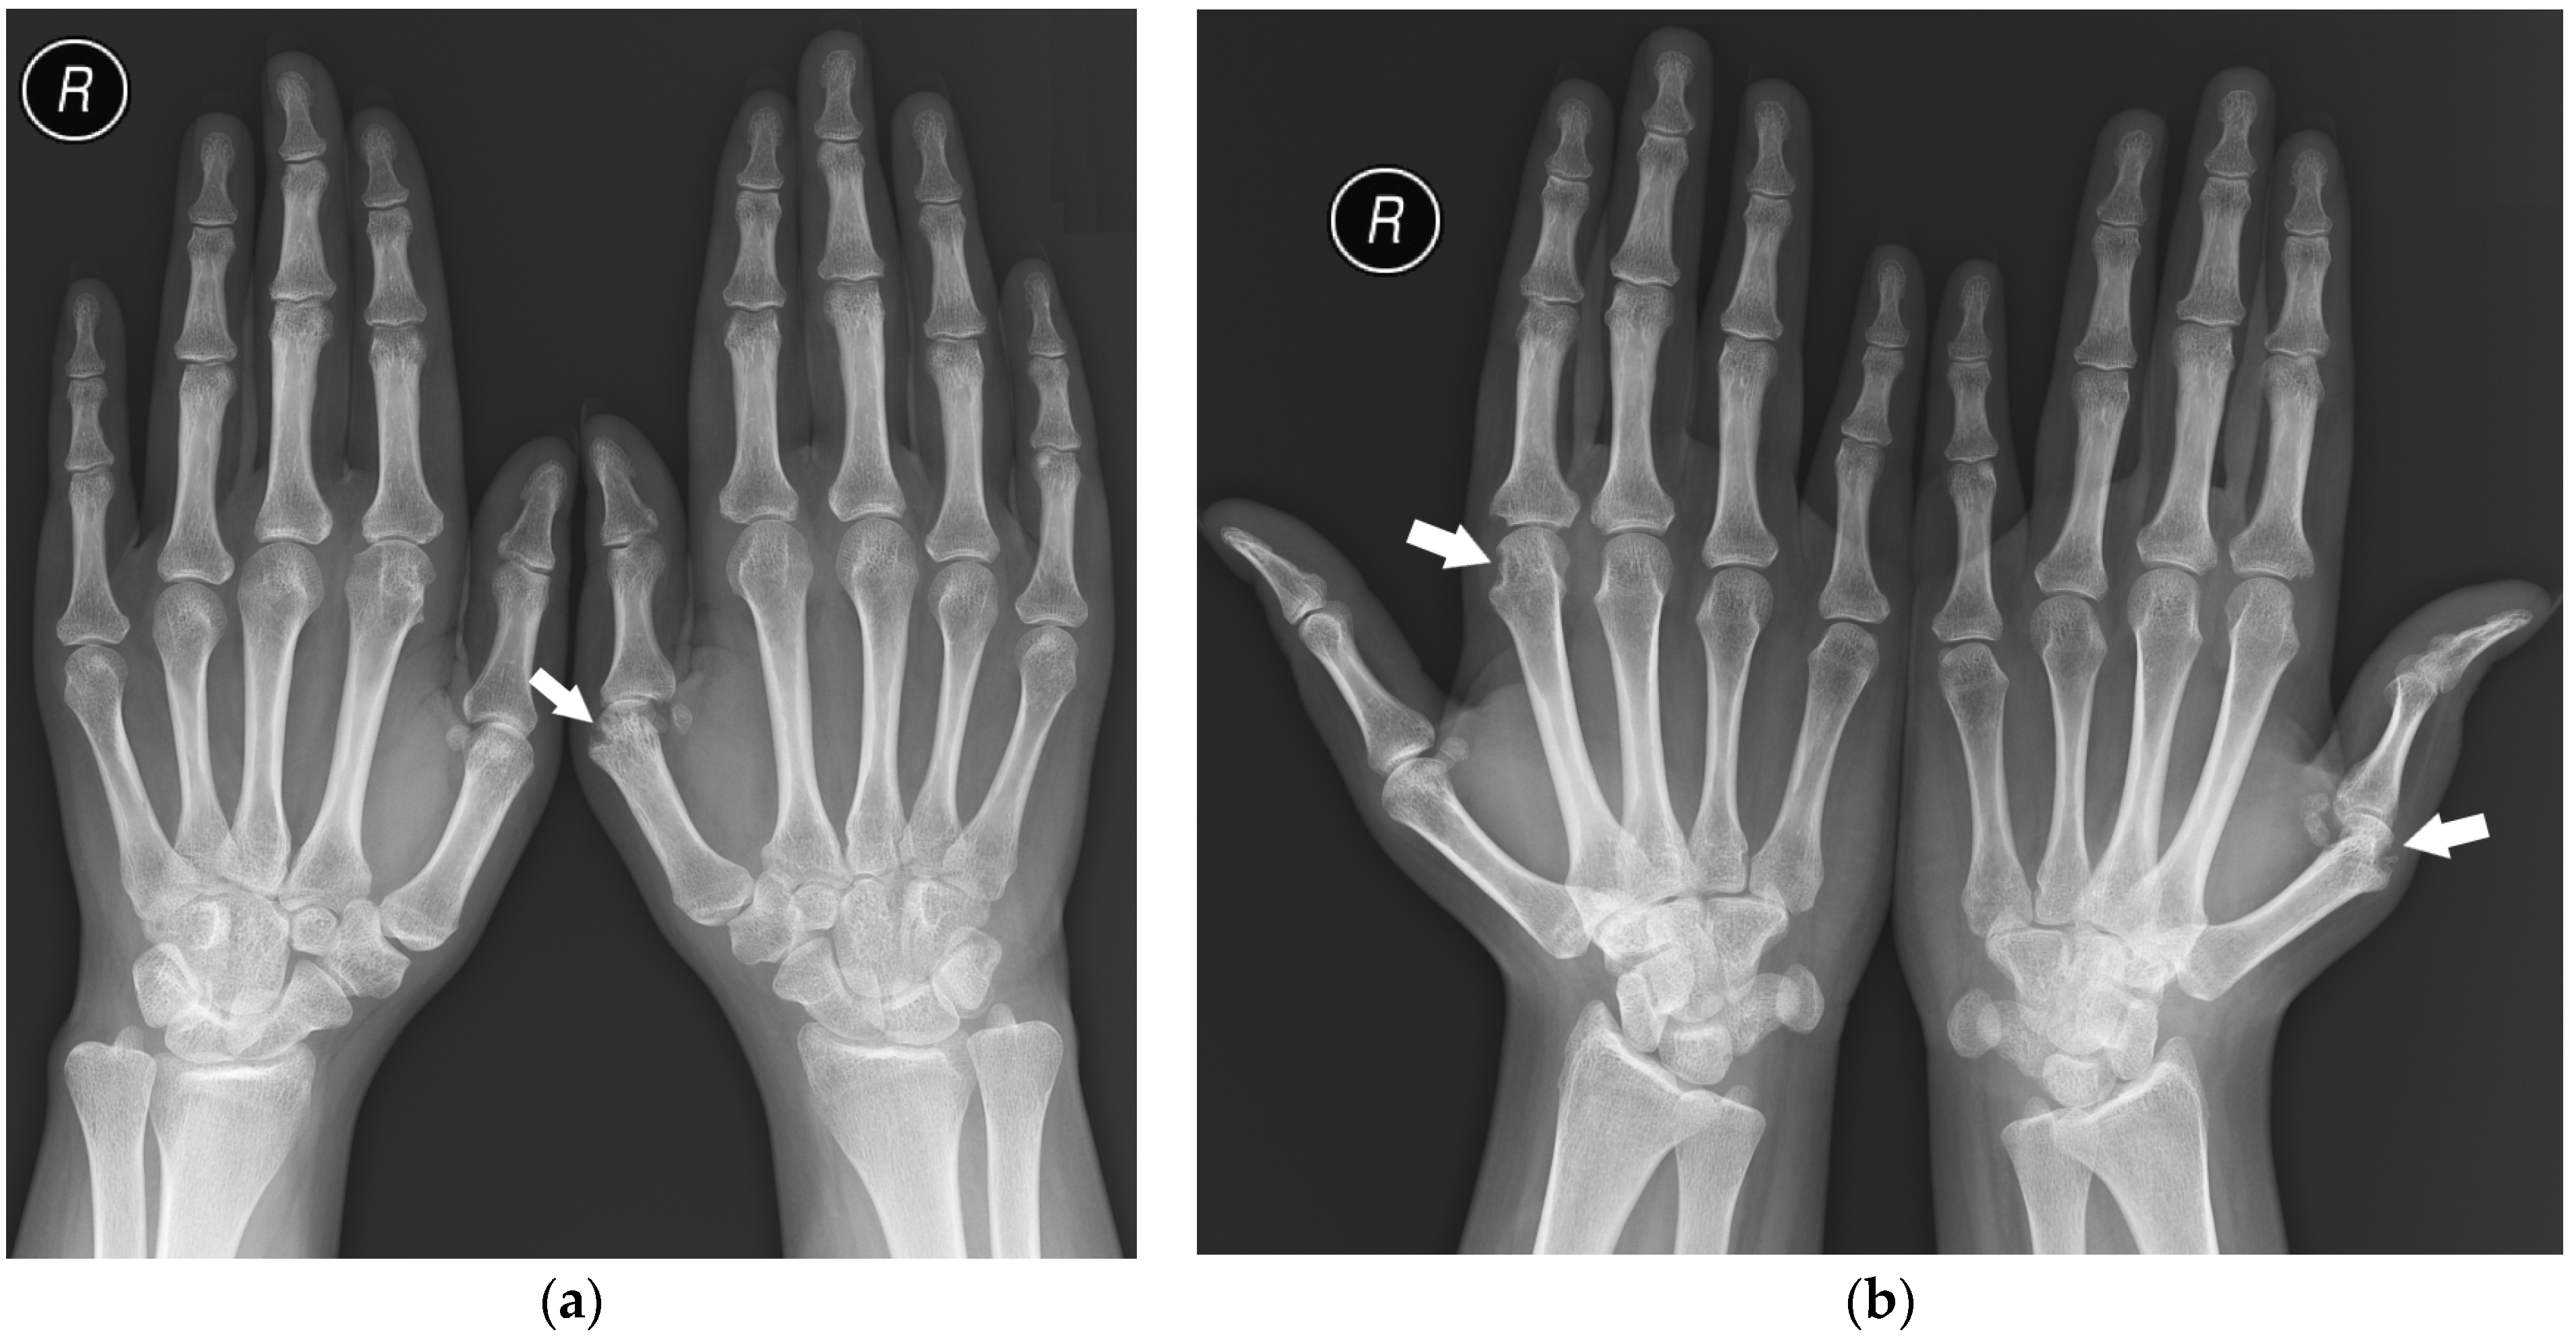

The analysis showed that seropositive and seronegative RA manifest symmetric involvement of corresponding compartments of both hands (Figure 7) more often than PsA, which is consistent with the literature [1,6,16]. The other considered types of symmetry were not proved to be statistically relevant.

Figure 7.

A 25-year-old female with seropositive RA. PA (a) and Nørgaard radiographs (b) of bilateral hands. Erosions, juxta-articular osteoporosis, joint space narrowing, and soft tissue swelling in several MCP joints, especially the left first MCP and right second MCP joints (arrows). Note the changes affecting the same compartments.

In our study, in 72% (111) of PsA patients, the DIP joints were not involved (Figure 8), without evidence of proliferative bone changes. This indicates the lack of the main hallmark of PsA, consisting of DIP involvement with concomitant proliferative and erosive changes. Therefore, these findings can easily mimic other rheumatic diseases, especially in the early stages of the disease, as mentioned by Sudoł-Szopińska et al. [15].

Figure 8.

A 31-year-old female with PsA. PA (a) and Nørgaard radiographs (b) of bilateral hands. Note the sparring of the DIP joints. There is soft tissue swelling and contracture at the level of the fourth and fifth digits on the PIP joints of the right hand (arrowheads). Note the soft tissue swelling around both wrists, especially on the ulnar side (white arrows). There are erosions at the base and head of the right fourth digit proximal phalanx with discrete proliferative bone changes (stars). Note the narrowing of the left fourth PIP and right second CMC joint spaces with bone cysts at the base of the right second MC bone (black arrow).